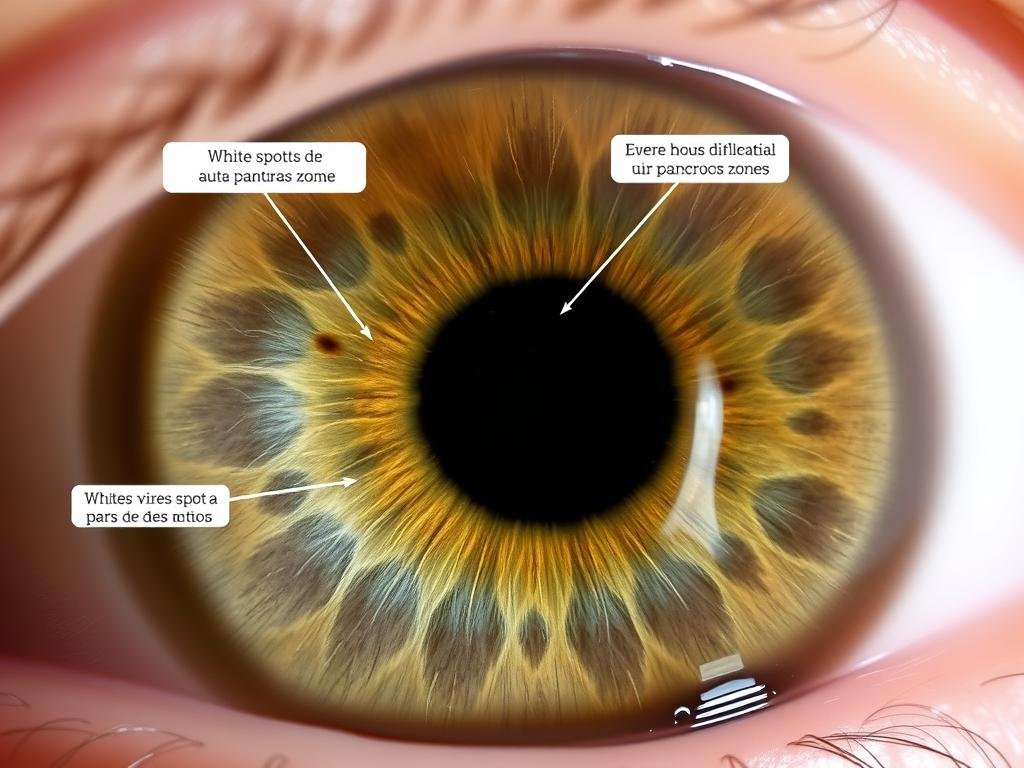

Iris con signos característicos de predisposición diabética

“En mi práctica clínica, he observado consistentemente que ciertos signos en el iris, como anillos de estrés en la zona correspondiente al páncreas y manchas blancas específicas, suelen preceder en 3-5 años a los diagnósticos formales de diabetes tipo 2. Esto nos da una ventana de oportunidad invaluable para implementar cambios preventivos.” – Dr. Carlos Mendoza, especialista en medicina integrativa

Caso 1: Detección precoz en paciente asintomático

Una mujer de 42 años sin síntomas aparentes acudió a una consulta rutinaria de lectura del iris. El análisis reveló signos de estrés pancreático y desequilibrios metabólicos característicos de prediabetes. Aunque sus análisis de sangre convencionales mostraban niveles de glucosa en el límite superior normal, aún no cumplía los criterios diagnósticos de prediabetes.

Siguiendo las recomendaciones basadas en la lectura del iris, implementó cambios significativos en su dieta y estilo de vida. En el seguimiento realizado 18 meses después, sus marcadores metabólicos habían mejorado notablemente y los signos de estrés en el iris habían disminuido, evitando potencialmente el desarrollo de diabetes tipo 2.

Caso 2: Complemento al diagnóstico convencional

Un hombre de 55 años con antecedentes familiares de diabetes tipo 2 presentaba resultados inconsistentes en sus pruebas de glucosa. La lectura del iris reveló patrones claros de disfunción pancreática y estrés metabólico crónico, lo que motivó una evaluación más exhaustiva.

Las pruebas especializadas posteriores confirmaron resistencia a la insulina en etapa temprana. La intervención temprana con un enfoque integrado, que incluía modificaciones dietéticas, suplementación específica y manejo del estrés, permitió estabilizar su metabolismo y prevenir la progresión a diabetes clínica.

Estos casos ilustran cómo la lectura del iris puede servir como una herramienta de detección temprana, especialmente valiosa para condiciones como la diabetes que se desarrollan gradualmente y donde la intervención precoz puede marcar una diferencia significativa en el pronóstico.